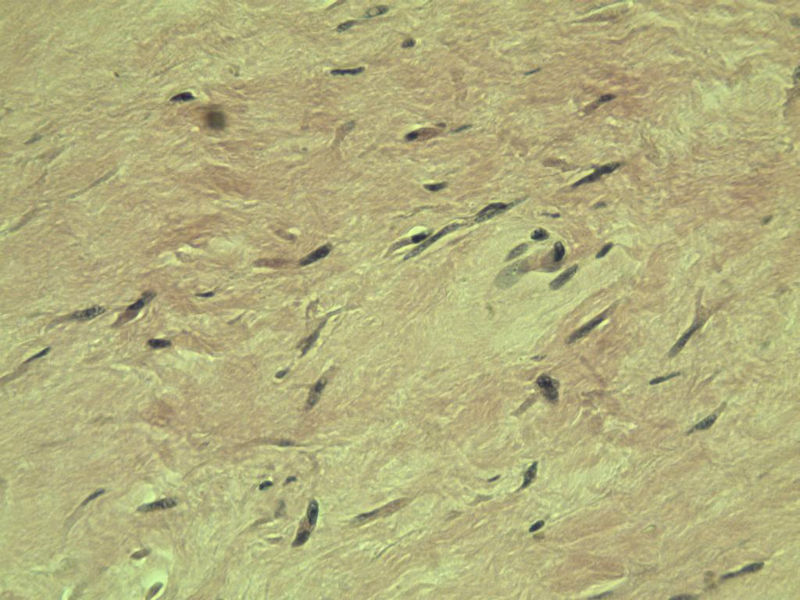

男,51岁, 4月前患者无意中发现右腘窝一包块,约核仁大小无疼痛, 4月来包块进行性生长

灰褐类圆形包块一个,直径 5 cm,切面灰白,实性,编织状。 请各位老师看看 是什么? 谢谢!